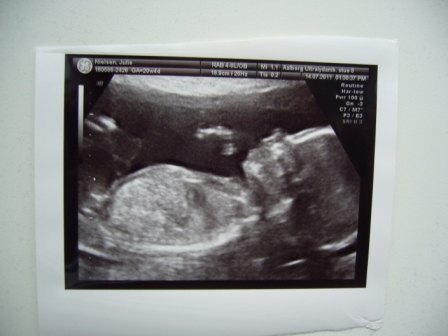

Ejh hvor skønt

Sikke en dejlig baby der ligger der! Ærgeligt du ikke fik overtalt kæresten, men tror nu også der er noget specielt ved først at få det af vide til fødslen

Tillykke med at du er over halvvejs (fedt!) og med en fiiin baby